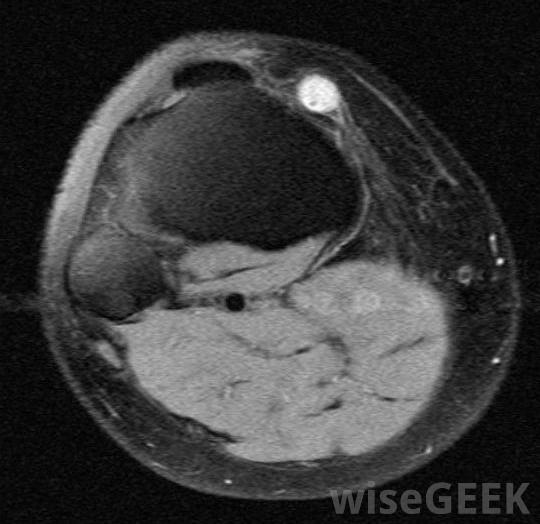

神经节囊肿的横截面,可导致手腕肿胀。在计算机用户中,腕管综合征(CTS)是导致手腕肿胀或手腕不适的常见原因。这种情况发生在手腕或手的正中神经受压时,导致射击痛、隐隐的搏动或全身疼痛。使用电脑鼠标或长时间打字可导致腕管综合征,患者通常需要改变自己的日常生活习惯,以防止病情复发。抗炎药也可以缓解病情,尽管这被认为是一种临时治疗,应该与长期措施相结合

神经节囊肿往往出现在手腕和脚踝上,并可导致关节疼痛和肿胀。